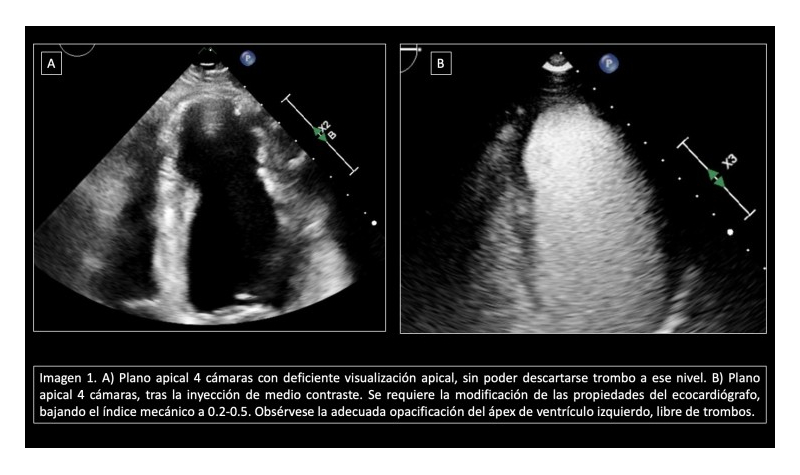

Para ello, la misma profesional se encargó de realizar una valoración clínica inmediata para descartar antecedentes de alergias medicamentosas y canalizar una vía venosa periférica. Junto con el equipo médico, se administraron 0.5ml de hexafloruro de azufre seguido de lavado con 5ml de suero salino, consiguiendo una adecuada opacificación de la región apical que permitió descartar la presencia de trombos (ver imagen 1).

Imagen 1